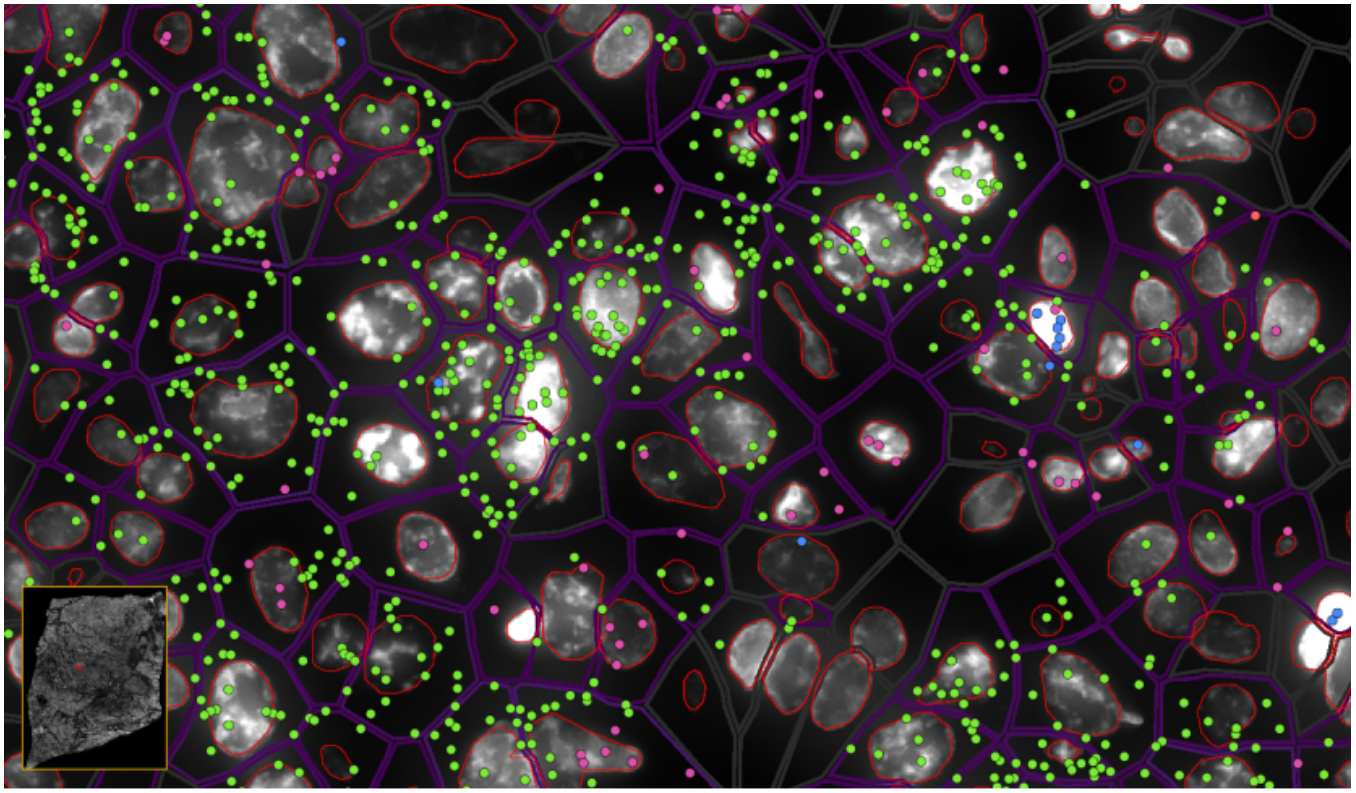

image.png

ͼ6-1£ºÊµÏÖµ¥Ï¸°û/ÑÇϸ°û·Ö±æÂʵĿռäת¼×é·ÖÎö £¬Â̵ã-EPCAM , À¶µã-KLRD1  £¬·Ûºìµã-LILRB2

ͼ6-2£ºÊµÏÖµ¥Ï¸°û/ÑÇϸ°û·Ö±æÂʵĿռäת¼×é·ÖÎö £¬Â̵ã-EPCAMת¼±¾